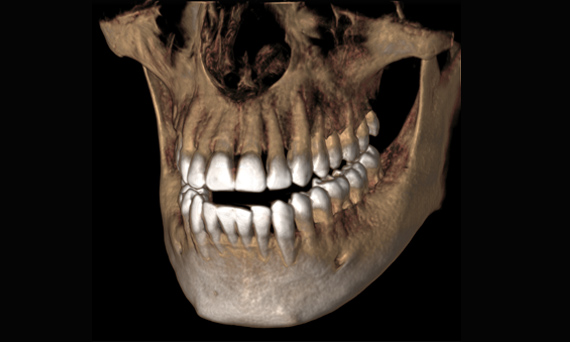

Imagen 3D: el futuro de la tecnología en obtención de imágenes

La tecnología 3D se está estableciendo cada vez más en los consultorios dentales en todo el mundo. Para diagnósticos más precisos y explicaciones del tratamiento, los rayos X en 3D ofrecen varias ventajas. Ya sea para dientes superpuestos, recorridos inesperados de los canales de los nervios, raíces ocultas o anomalías de las articulaciones temporomandibulares, las imágenes en 3D tienen un valor inestimable para un gran número de diagnósticos.

Orthophos SL 3D ofrece una gran variedad de opciones para satisfacer estas necesidades: diferentes tamaños de volumen donde elegir, modos HD/SD/Dosis bajas de radiación y un software inteligente e intuitivo para aprovechar al máximo las imágenes obtenidas y vincularlas directamente al tratamiento.

Galería de muestra de imágenes panorámicas 3D